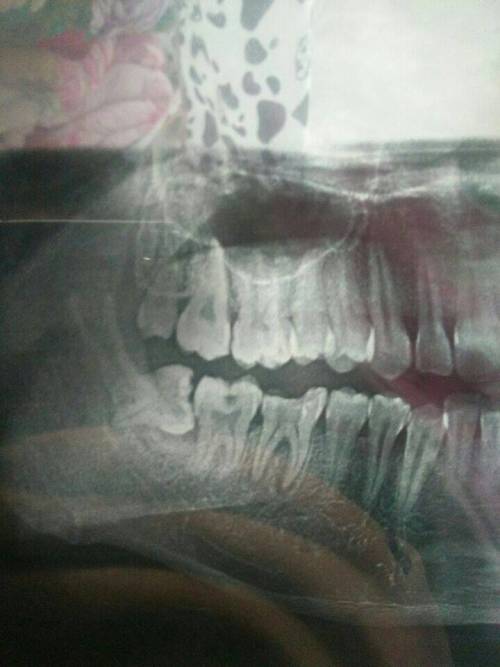

2、手術復雜性:拔智齒手術的復雜性也會影響費用,如果智齒生長位置正常,手術相對簡單;如果智齒被埋在骨頭里,需要切開牙齦和骨頭,手術難度增大,費用相應增加。

1、術前檢查:拔智齒前需要進行口腔檢查、X光片等檢查,以了解智齒的位置和周圍結構,這些檢查費用也是拔智齒總費用的一部分。